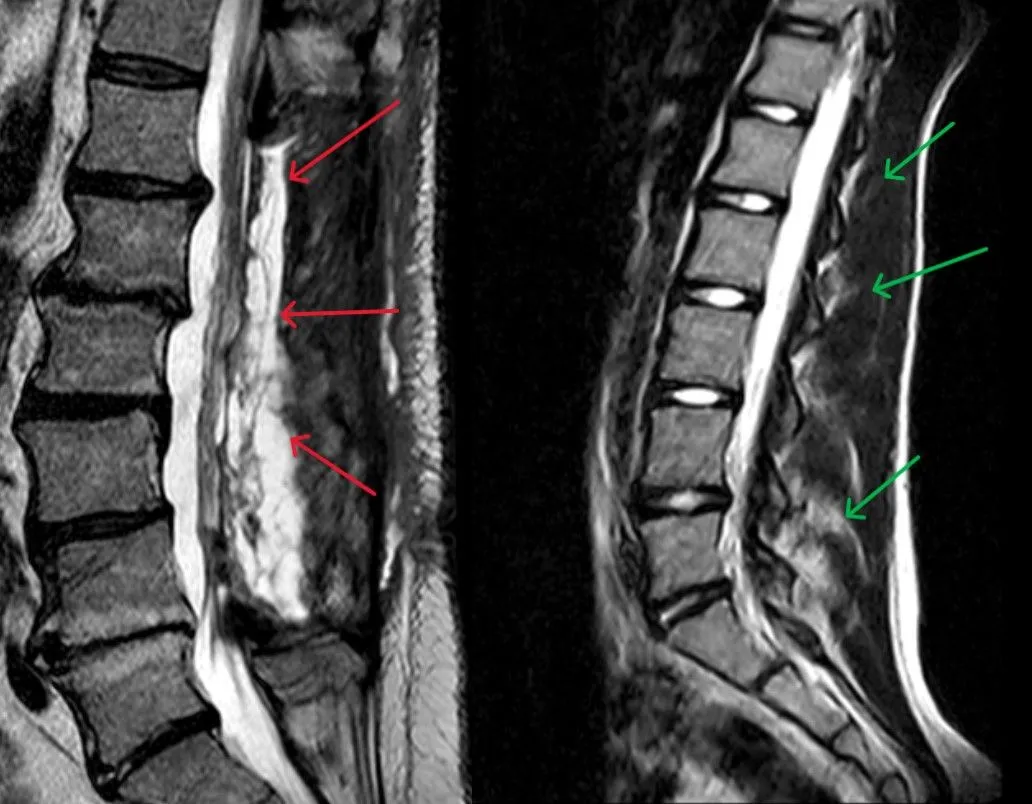

#Laminectomy-MuscleDamage-Annotated.jpg